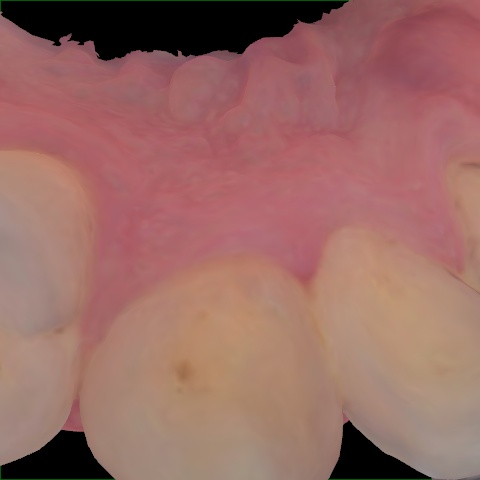

Image 74 / 2000

NHD39969

Annotated as "Good"

Original Image Rendering Image